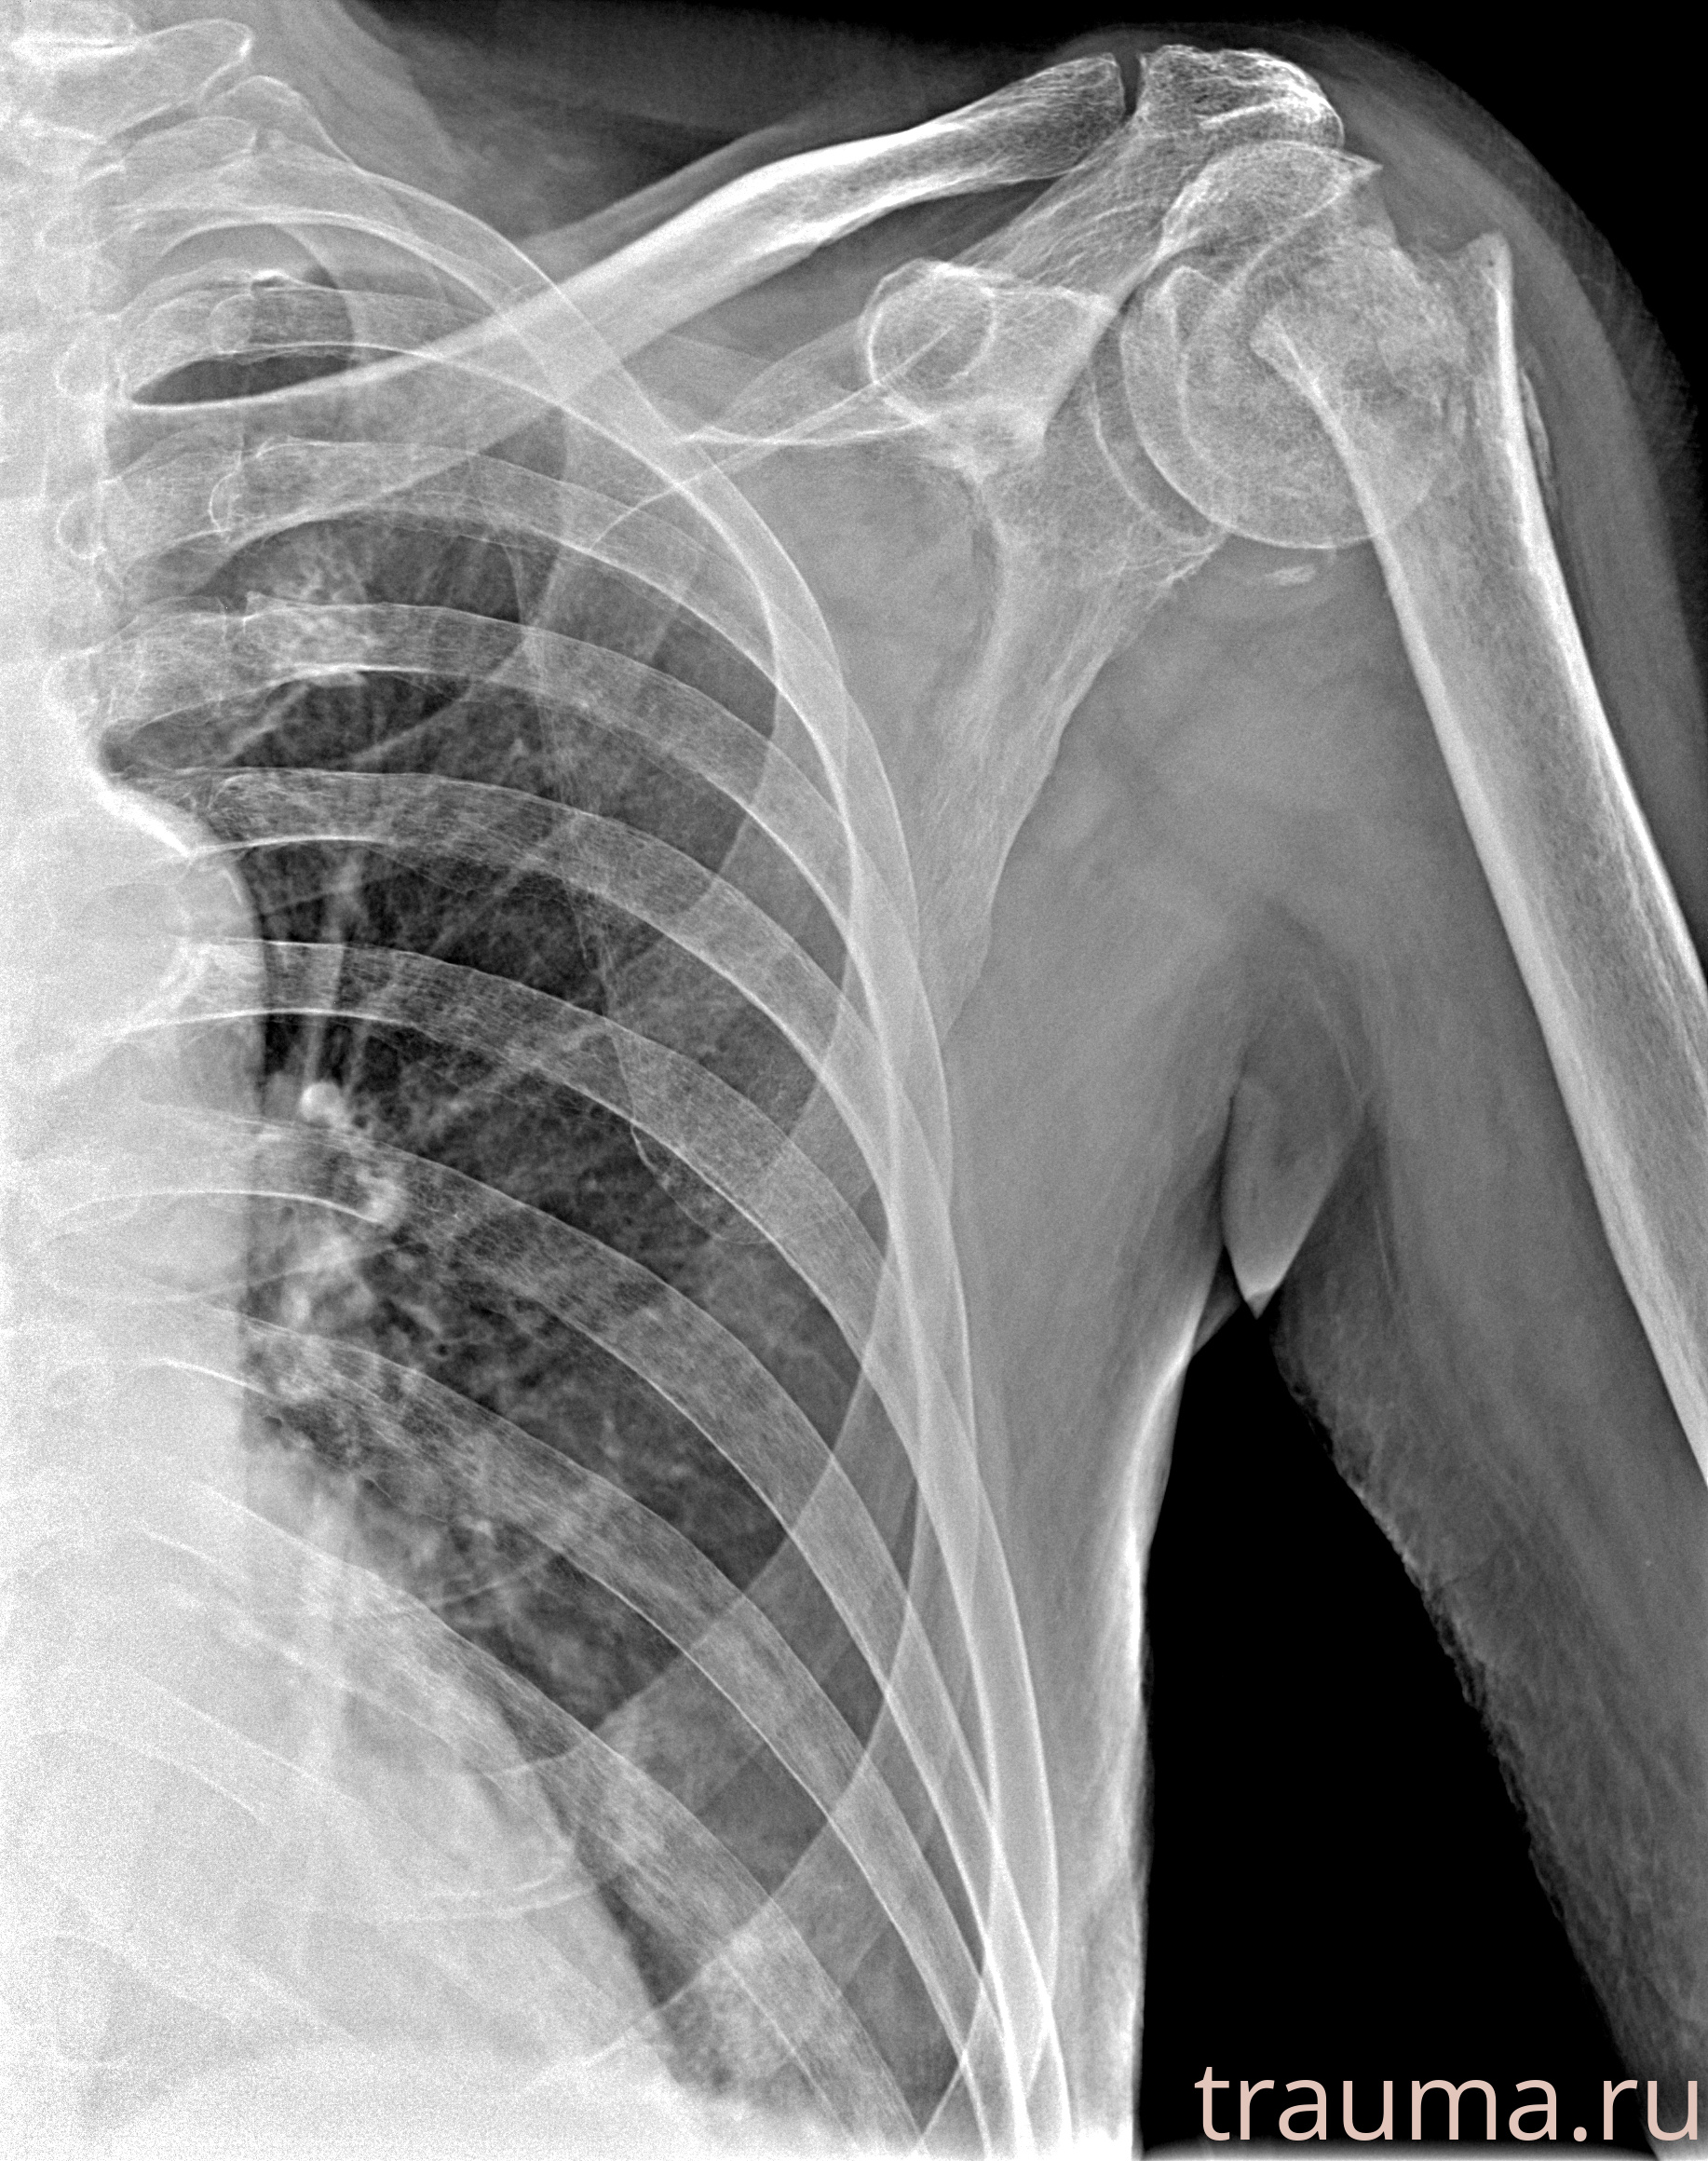

Рентгенограммы

Рентген на дому: по вашему адресу приезжает врач-рентгенолог, травматолог-ортопед с мобильным рентгеновским аппаратом, проводит диагностику травмы или заболевания, делает необходимые рентгенограммы, дает рекомендации по дальнейшему лечению. Получить качественные снимки в домашних условиях возможно благодаря уникальной методике, разработанной МосРентген Центром для института  Склифосовского